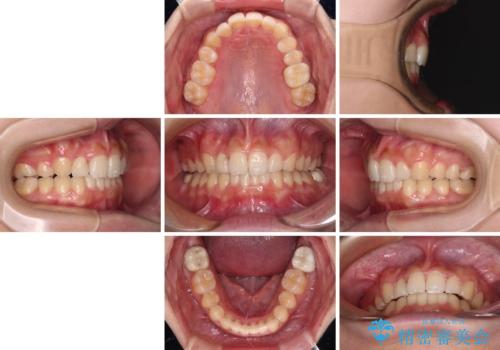

気になる八重歯を改善 補助装置併用のインビザライン治療

- 上顎の重なっている前歯を気にして来院された患者様です。

八重歯改善には抜歯が必要で、八重歯の移動量が多く、更には右側にずれている正中を改善する必要がありました。